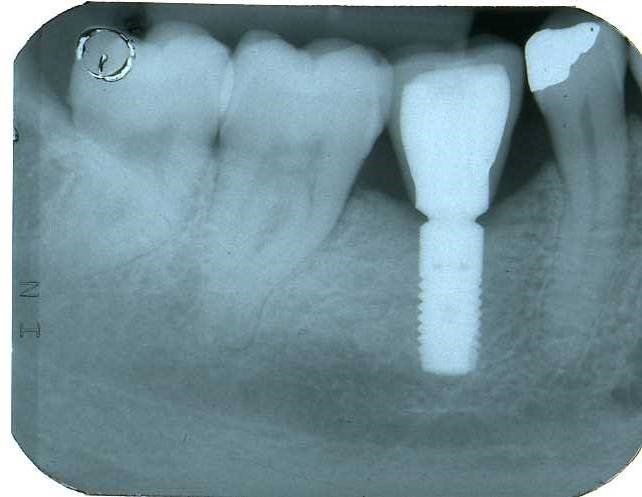

Nel 1994 una paziente di 28 anni subì la frattura dell’incisivo centrale superiore sinistro precedentemente trattato endodonticamente

Un caso analogo al precedente.

Una giovane signora di ventotto anni subisce nel 1996 la frattura dell’incisivo centrale superiore destro

in precedenza trattato endodonticamente